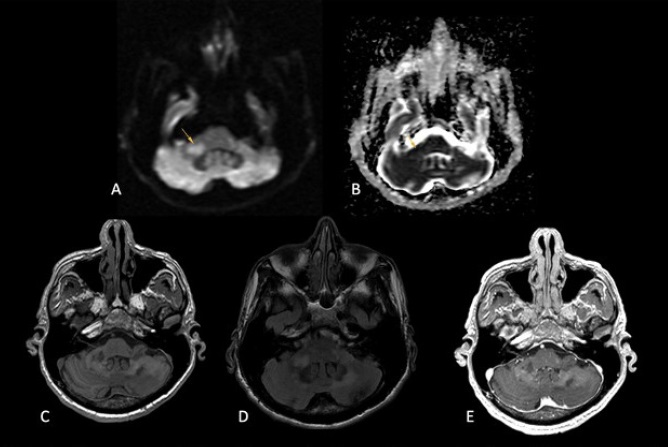

Realizamos resonancia magnética de encéfalo con medio de contraste (gadolinio) documentando cambios en la intensidad de señal en secuencias T2 y FLAIR, infratentoriales, hacia los pedúnculos cerebelosos; lesión nodular derecha con restricción en difusión/ADC (Imagen 1). La lesión cerebelosa izquierda fue la de mayor tamaño (Imagen 2); ninguna de las lesiones presentó reforzamiento con el paso de medio de contraste y, a pesar de la extensión de las lesiones, no se documentó efecto de masa sobre las estructuras adyacentes. Estos hallazgos suguirierón leucoencefalopatía multifocal progresiva.

Imagen 2 LMP con afectación infratentorial. Involucro a los pedúnculos cerebelosos. A y B. La lesión (flecha) muestra restricción a la difusión. C. Hipointensidad en T1, D. Hiperintensidad en FLAIR. Destaca que ninguna de las imágenes presenta efecto de masa. E. T1 poscontraste sin reforzamiento.